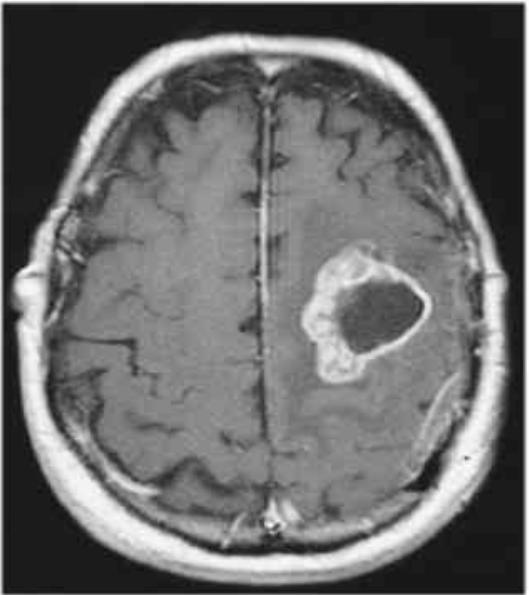

Vous suspectez fortement une HTIC et réalisez une IRM cérébrale que voici.

ici, nous retrouvons une IRM cérébrale en coupe FLAir (Séquence antianatomique comme un T2 et suppression du signal du LCR (ventricules et sillons corticaux)) qui montre une masse :

Étape 1 : caractériser la masse

Gauche

Centre en hyposignal probablement nécrotique

Contours en hypersignal avec oedème péri-lésionnel

Ces caractéristiques sont celles d’une masse avec un aspect en cocarde (image ovalaire à centre en hyposignal et contours en hypersignal)

Étape 2 : connaitre les causes à évoquer devant une image en cocarde :

• Glioblastome

• Métastase cérébrale

• Abcès cérébral

• Lymphome

• Toxoplasmose

Attention cette liste n’est pas exhaustive mais ce sont les principales causes à évoquer devant ce type d’image.